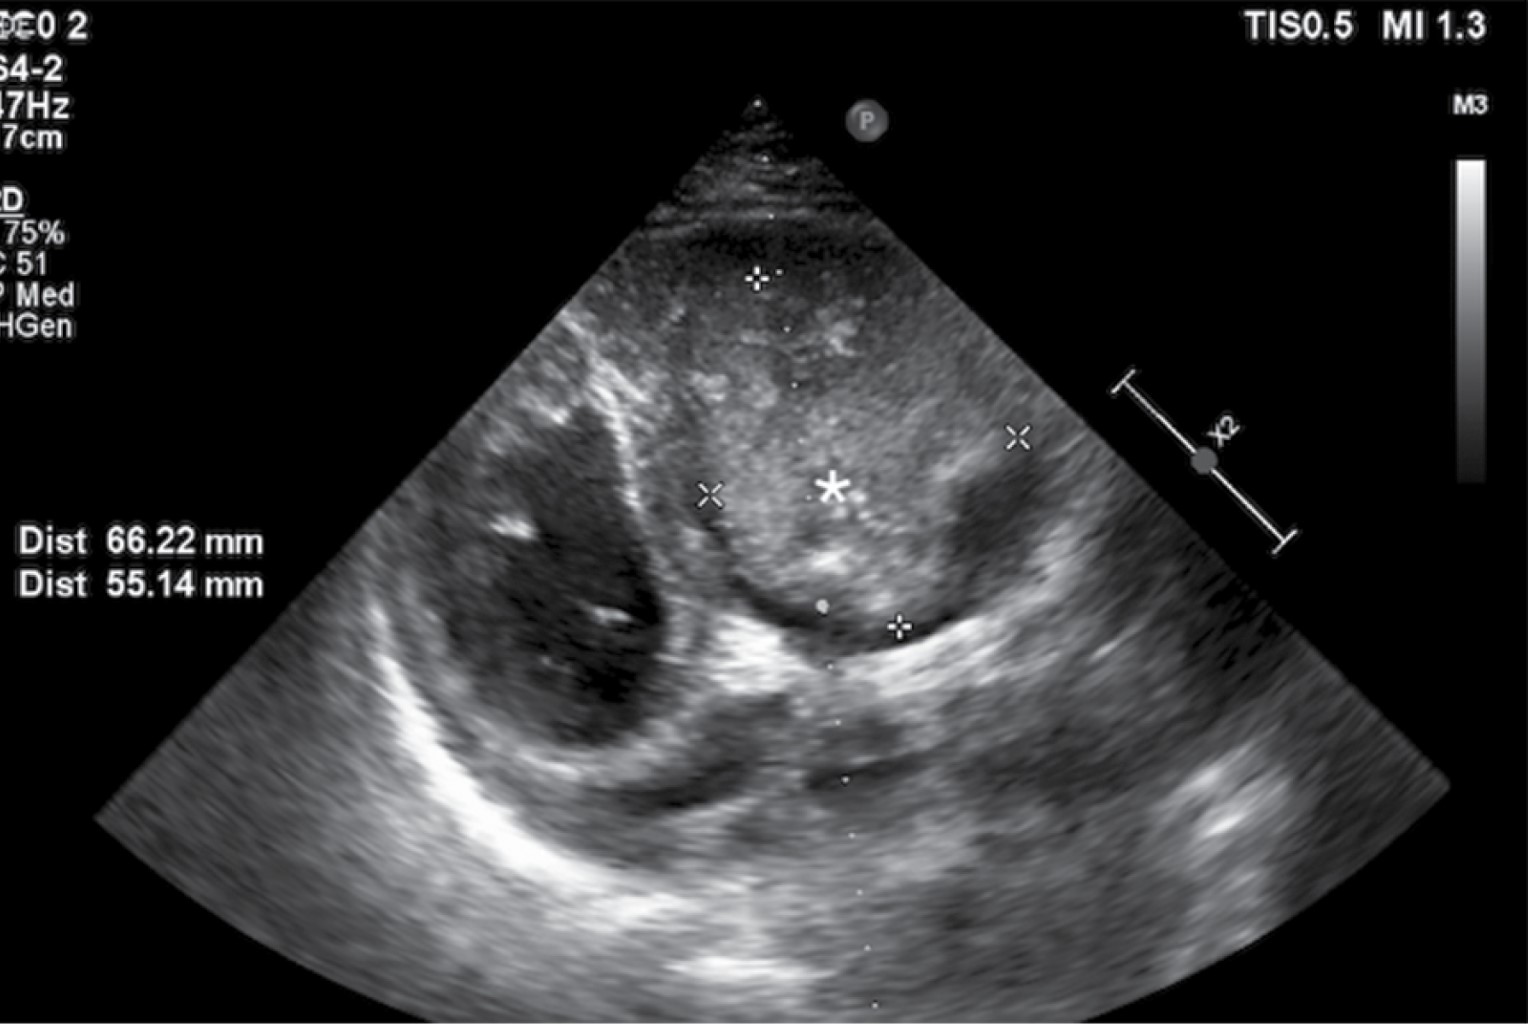

Enorme masa ventricular derecha en un paciente masculino de 25 años

Un joven varón acudió al Servicio de Urgencias del Hospital Santa Marcelina de Cidade Tiradentes con signos de insuficiencia cardíaca congestiva y pérdida de apetito. Se realizó un ecocardiograma bidimensional y se detectó una enorme masa ventricular derecha. Las masas cardíacas son siempre un desafío, y este artículo proporciona una revisión sobre el tema.

Figura 4